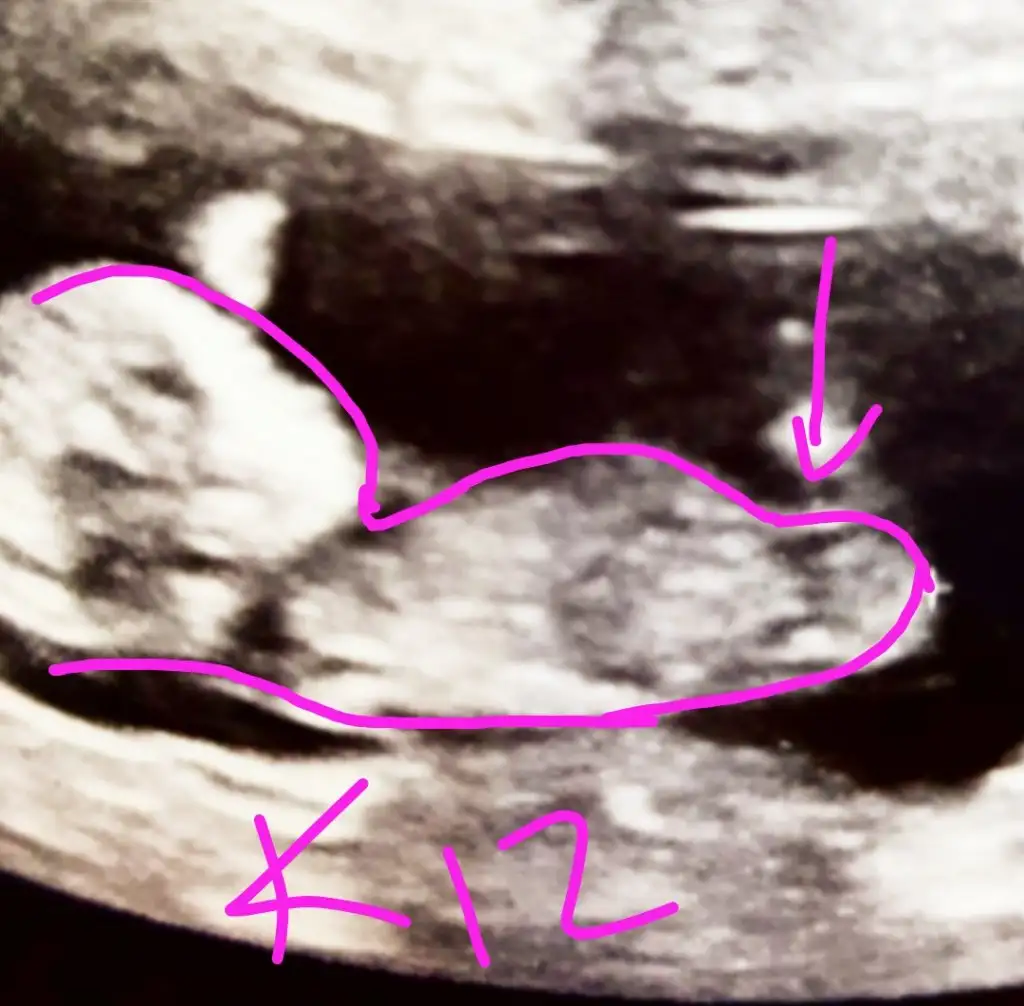

Aslında okla gösterdiğiniz yeri ben ayak olarak düşündüm deKız gibi geldi nubu banaumarım gonlunuzdeki olsun inşallahEki Görüntüle 2748350

Kız gibi sanki. Başka USG varsa paylaşın emin olamadım

Kız gibi sanki. Başka USG varsa paylaşın emin olamadım![]()

USG net değil gördüğüm nub ise erkek sanki kaç haftalık USG